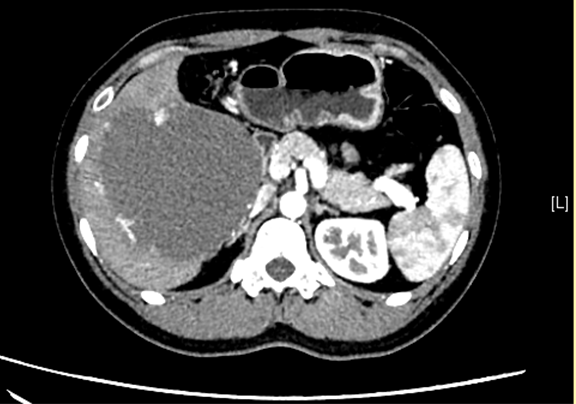

现病史:患者1月前无明显诱因出现右上腹饱胀感,伴右侧肩背不适,伴恶心、嗳气,伴头晕、乏力,无发热,无心悸,无呕吐、呕血,无反酸、烧心,无心慌、胸闷、胸痛,无咳嗽、咳痰,无腹泻、便秘,于当地医院就诊,行“抗炎”治疗(具体不详),疗效不佳。今患者为求进一步治疗,遂来我院,门诊行上腹部增强CT检查示:肝右叶巨大占位,血管瘤可能性大。

辅助检查: 下腹部增强CT示:肝右叶巨大占位。

术前CT检查:动脉期

静脉期

平衡期